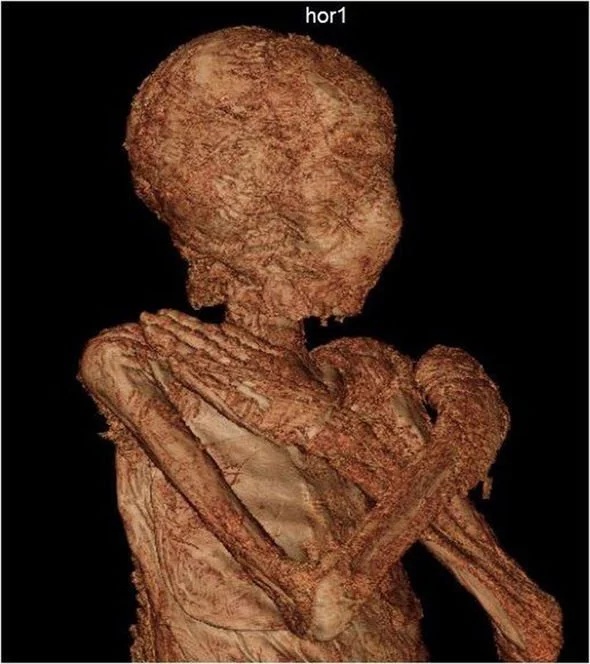

The woman is believed to have been no older than 30 when she passed away and was at least 28 weeks into her pregnancy. Archaeologists at the National Museum in Warsaw, Poland, announced the unexpected discovery this week, just five years after another major breakthrough was made. The first-century BC mummy has been in the museum’s collection since 1917, although until 2016 it was believed to belong to a man.

The study states: “She came from the elite of the Theban community and was carefully mummified, wrapped in fabrics, and equipped with a rich set of amulets.

“Closer examination revealed that the woman passed away between 20 and 30 years of age, together with a child estimated to be between the 26th and 30th week of development.

“This find is the only known case of an embalmed pregnant individual.”

Until recently, hieroglyph inscriptions on the mummy’s sarcophagus suggested the remains belonged to the priest Hor-Djehuti.